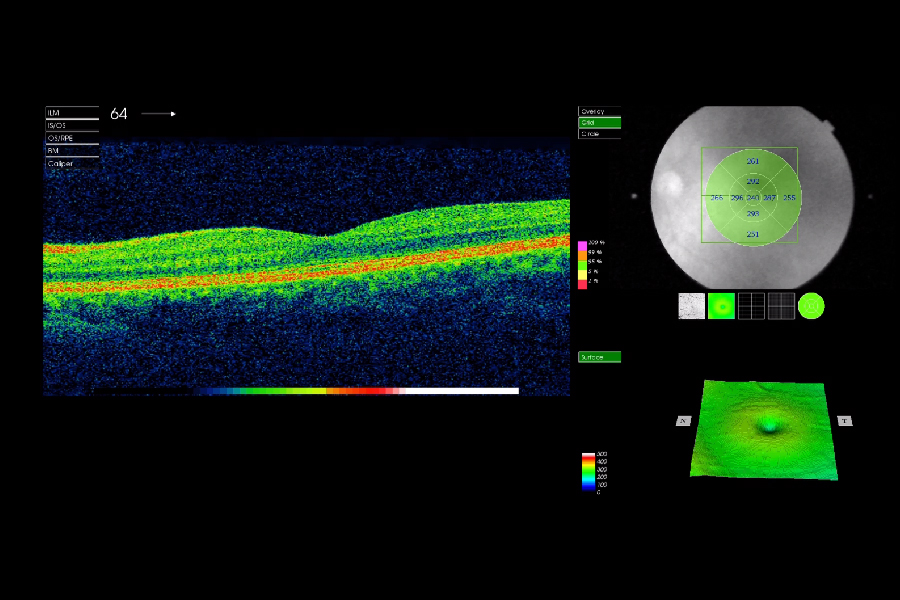

Virtuálna prehliadka vyšetrenia z očnej optiky na dvoch rozdielnych prístrojoch. Čo vidí optometrista, kým my sledujeme svetlo z prístroja? Čo z daného obrazu vie vyčítať? Čo všetko dokážu tieto prístroje? Klient môže prvýkrát vidieť postup vyšetrenia ,,očami lekára" prostredníctvom prehliadky prednej a zadnej časti oka s rozkliknuteľnými definíciami.